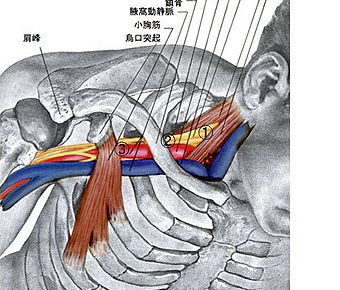

こんばんは!横浜本牧パーソナルトレーナー宮原崇です。 朝もすっかり寒くなり、自転車通勤には手袋が必要になってくる季節だと思うと、時が過ぎる早さにまたまた驚かせれました。 さて、昨日は頚椎由来のしびれを書かせていただきまし…

解剖学

解剖学